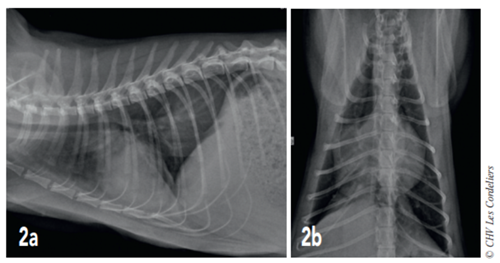

Un examen radiographique thoracique est réalisé (Fig. 1a et 1b) : il montre la présence d’une dilatation modérée des artères pulmonaires plus accentuée dans les lobes crânial droit et caudal gauche ; la silhouette cardiaque est élargie avec un vertebral heart size (VHS) = 9,8 (VU : 7,5 ± 0 3) 2 ; un épanchement pleural modéré associé à un arrondissement des bords pulmonaires responsable d’une opacité interstitielle modérée est mis en évidence. Il est observé une hépatomégalie modérée.

Fig. 1a – Radiographie thoracique de profil droit du 07/08/2017 : cardiomégalie (VHSM 9,8 ; VU : 7,5 ± 0,3 A.L. Lister), dilatation artérielle pulmonaire modérée, consolidation du lobe pulmonaire moyen droit et épanchement pleural modéré.

Fig. 1b – Radiographie thoracique de face du 07/08/2017 : cardiomégalie (silhouettecardiaque > 2/3 de la largeur thoracique), dilatation artérielle pulmonairemodérée,consolidation du lobe pulmonaire moyen droit et épanchement pleural modéré.